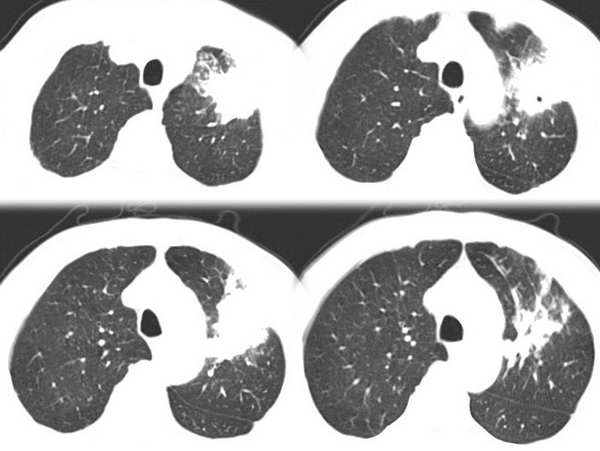

男,58岁,咳嗽1月加重1周,伴痰中带血

左肺上叶胸膜下不规则团块阴影,内见空泡,边缘光整,肺纵比率>50%,支持左肺癌的诊断。

ct:左上肺块状影、其内徐点状气体外蜜度大致均匀。周围粗大索状影

其内透光影仔细观察像是支气管,病灶周围有渗出改变,该病灶不考虑感染性病变,机化性肺炎能排除吗

理由:1 病灶有恶性肿瘤的特征:空泡征,毛刺,棘状突起

左上肺病灶与胸膜脂肪线存在,未见明显胸膜凹陷征,虽然病灶边缘不规则,但未见明显“短毛剌、切迹征、免耳征、血管束集征”,其间亦见条索状、斑点状影,认为左上肺结核或炎性病变>周围型肺癌。

病灶比较虚 周围有明显渗出 卫星灶及条素影 病灶边缘有棘突 胸膜外脂肪层存在考虑结核

考虑肺结核可能性大。理由1.病灶形态不规则,其周有卫星灶,2.病灶没有毛刺征,灶周出现粗大索条影.